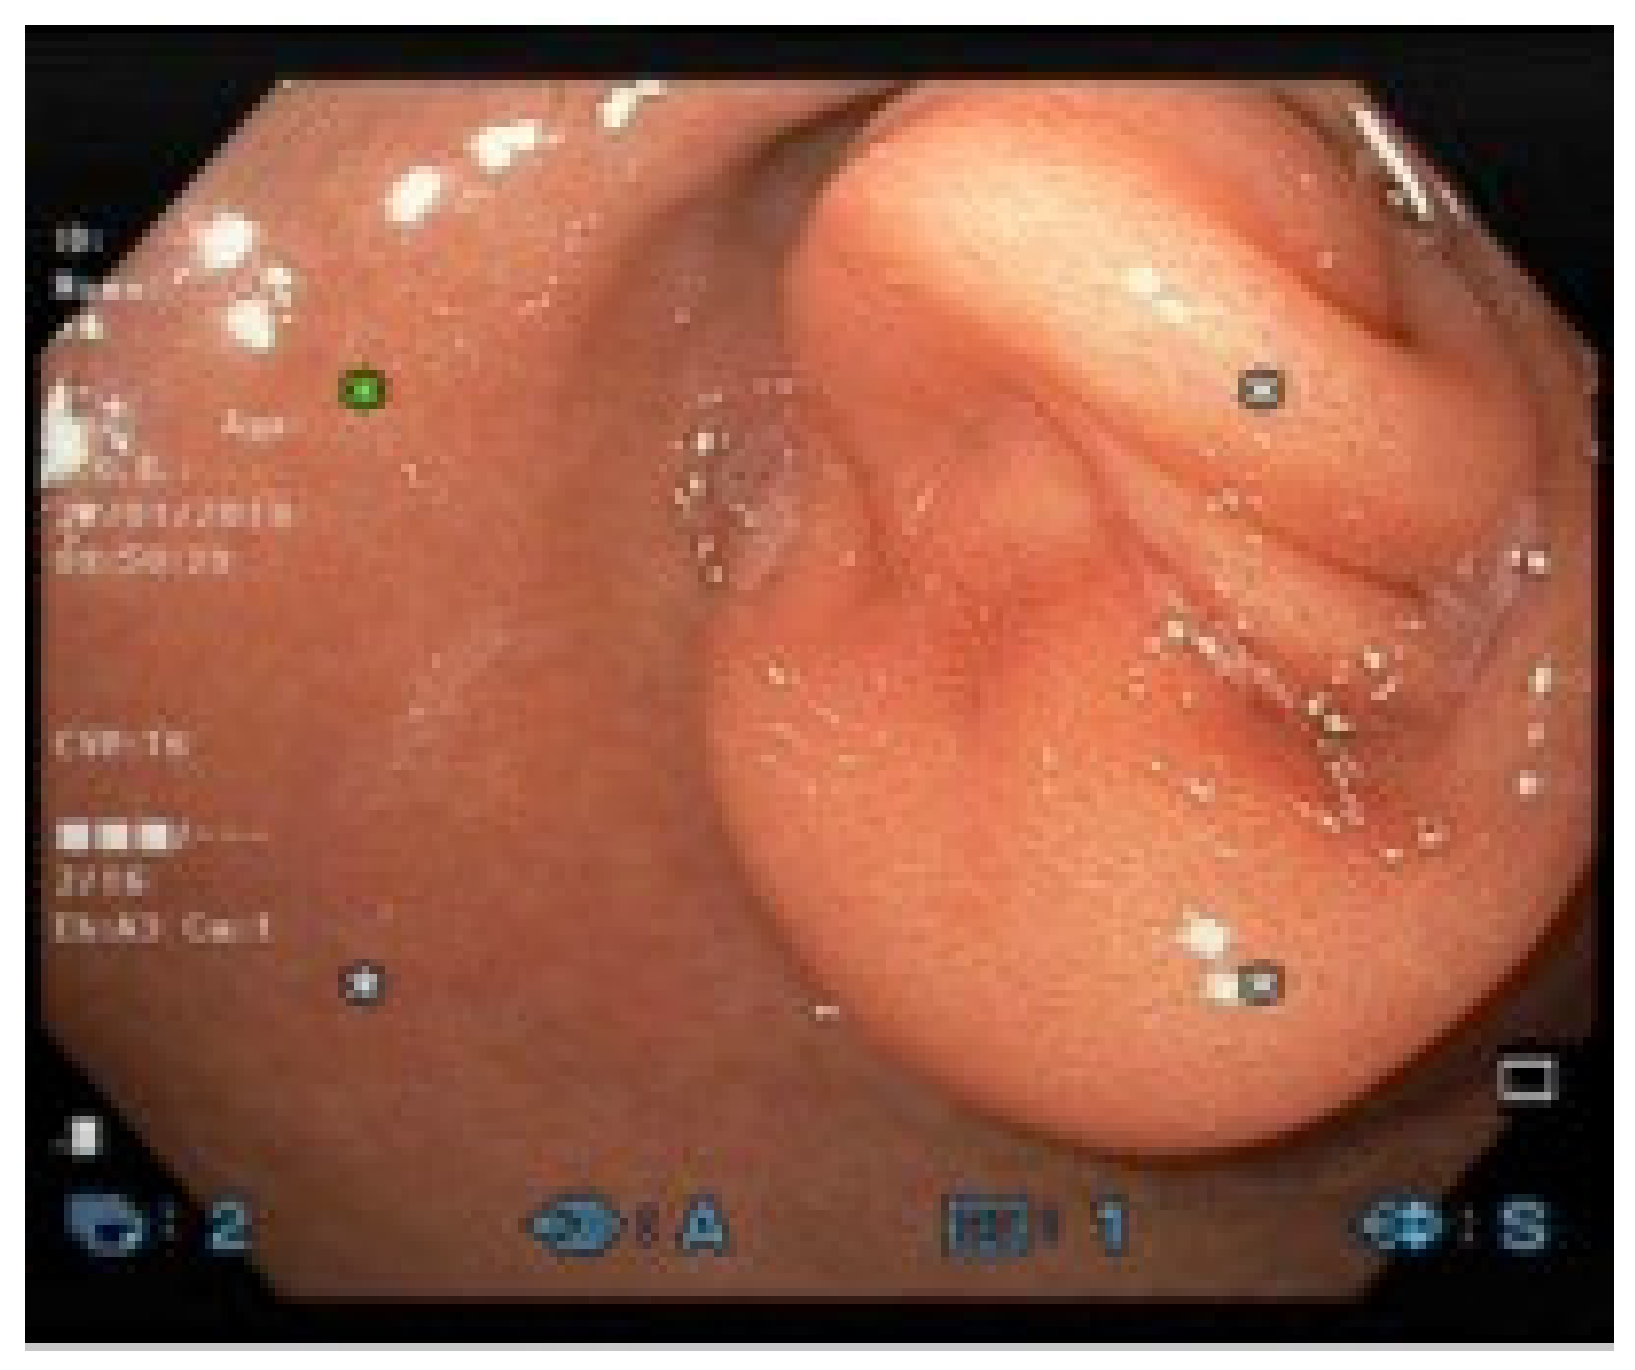

2. Case Report